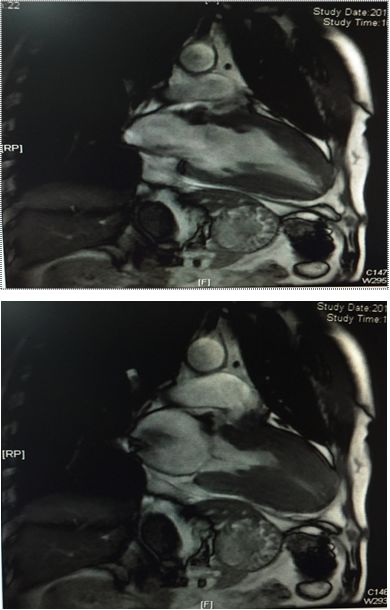

左房饱满,左室不大,前间隔及其余左室各中远段及心尖部增厚(最厚16-21mm)

舒张期心尖呈“黑桃尖”样改变,收缩末左室腔中部几近闭塞,心尖室腔呈裂隙样

左室基底段厚度大致正常或高限,收缩功能大致正常,左室流出道未见梗阻征象

右房、右室不大,右室壁未见脂肪浸润,右室收缩功能大致正常,右室流出道未见梗阻征象

二尖瓣少量反流,三尖瓣及主动脉瓣活动未见异常,心包无增厚,主肺动脉直径25mm,同水平升主动脉直径28mm

心肌首过灌注左室心尖部可见心内膜下灌注减低

延迟扫描室间隔远段及左室心尖部可见心内膜下强化信号

冠状动脉分布呈右优势型

左、右冠状动脉主干及分支管壁光滑,管腔通畅,未见明确有意义狭窄及阻塞性病变

左心室室壁普遍增厚,以室间隔为著,可见梗阻存在